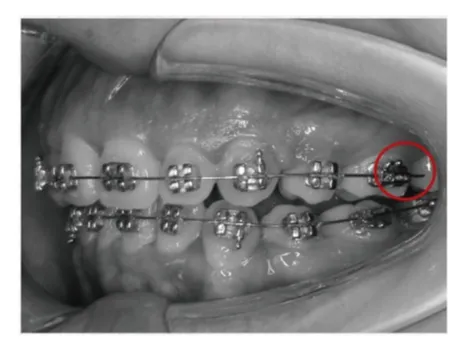

03、轻松牵引

解决压痕困扰,有效消除压痕问题、享受卓越矫正效果

满足各种牵引需求,有效减少各种弓丝弯制、有效控制牵引压痕